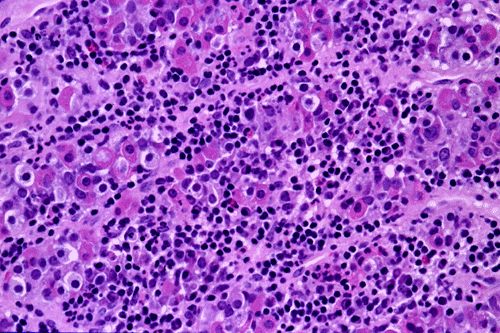

Low-magnification (Panel B ) of the frozen sections shows anterior pituitary tissue infiltrated by lymphocytes with  formation of lymphoid aggregates. On high-magnification (Panel C)the epithelial cells nests are composed of cells with amphophhilic or eosinophilic cytoplasm. These cells are the residual anterior pituitary cells. The presence of different cell types but not a monotonous cell type indicated that the lesional tissue is non-neoplastic anterior pituitary tissue. An inflammatory infiltration composed predominantly of lymphocytes and small number of polymorphonuclear leukocytes is present. It appears that some of the epithelial cell nests are infiltrated by inflammatory cells. Note that the cytologic features of these cells are much better preserved in the (Panel A). As a general rule in intro-operative consultation in surgical neuropathology, the cytologic preparation provides the cytologic details and the frozen sections provide the architectural (histologic) information.

The histopathology of lymphocytic hypophysitis is well illustrated in this case. In essence, there is a lymphoplasmacytic infiltrate in a background of adenohypophysial tissue. There is a variable number of neutrophils, eosinophils, and histiocytes. Lymphoid aggregates are common features. The infiltrating lymphocytes are polyclonal in nature and can be well demonstrated by immunohistochemistry. This is a useful feature that distinguish lymphocytic hypophysitis from neoplastic lymphoproliferative disorders. A variable degree of fibrosis and atrophy of the adenohypophysial tissue tissue can be seen. The residual adenohypophysial epithelial cells may exist as small islands and may show oncocytic changes.